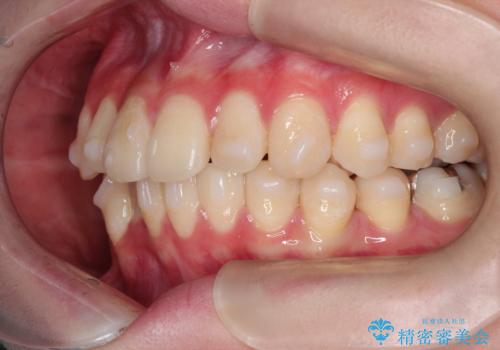

- 上下の前歯に捻れ(捻転)とガタつき(叢生)が見られます。

上の2番目の前歯の捻れに関しては、元々歯の大きさが小さい歯であるため、マウスピースにて力がかかりにくく、捻転の改善が一般的に難しくなりがちです。

下の犬歯に関しても捻れと傾き、ガタつきが大きく、歯根の長さも相まって移動の難易度が高くなりがちです。

インビザラインのそうした特色を踏まえた上で、それらをリカバーできるように治療方式の調整を十分に行い、治療を進めました。

マウスピース枚数 初回33枚 +追加22枚 +追加31枚

概ね2年で治療完了しました。

マウスピース矯正の特性として動かすのが難しい歯を含むケースでしたが、当院独自の工夫を随所に盛り込み、狙い通りの治療結果が得られました。